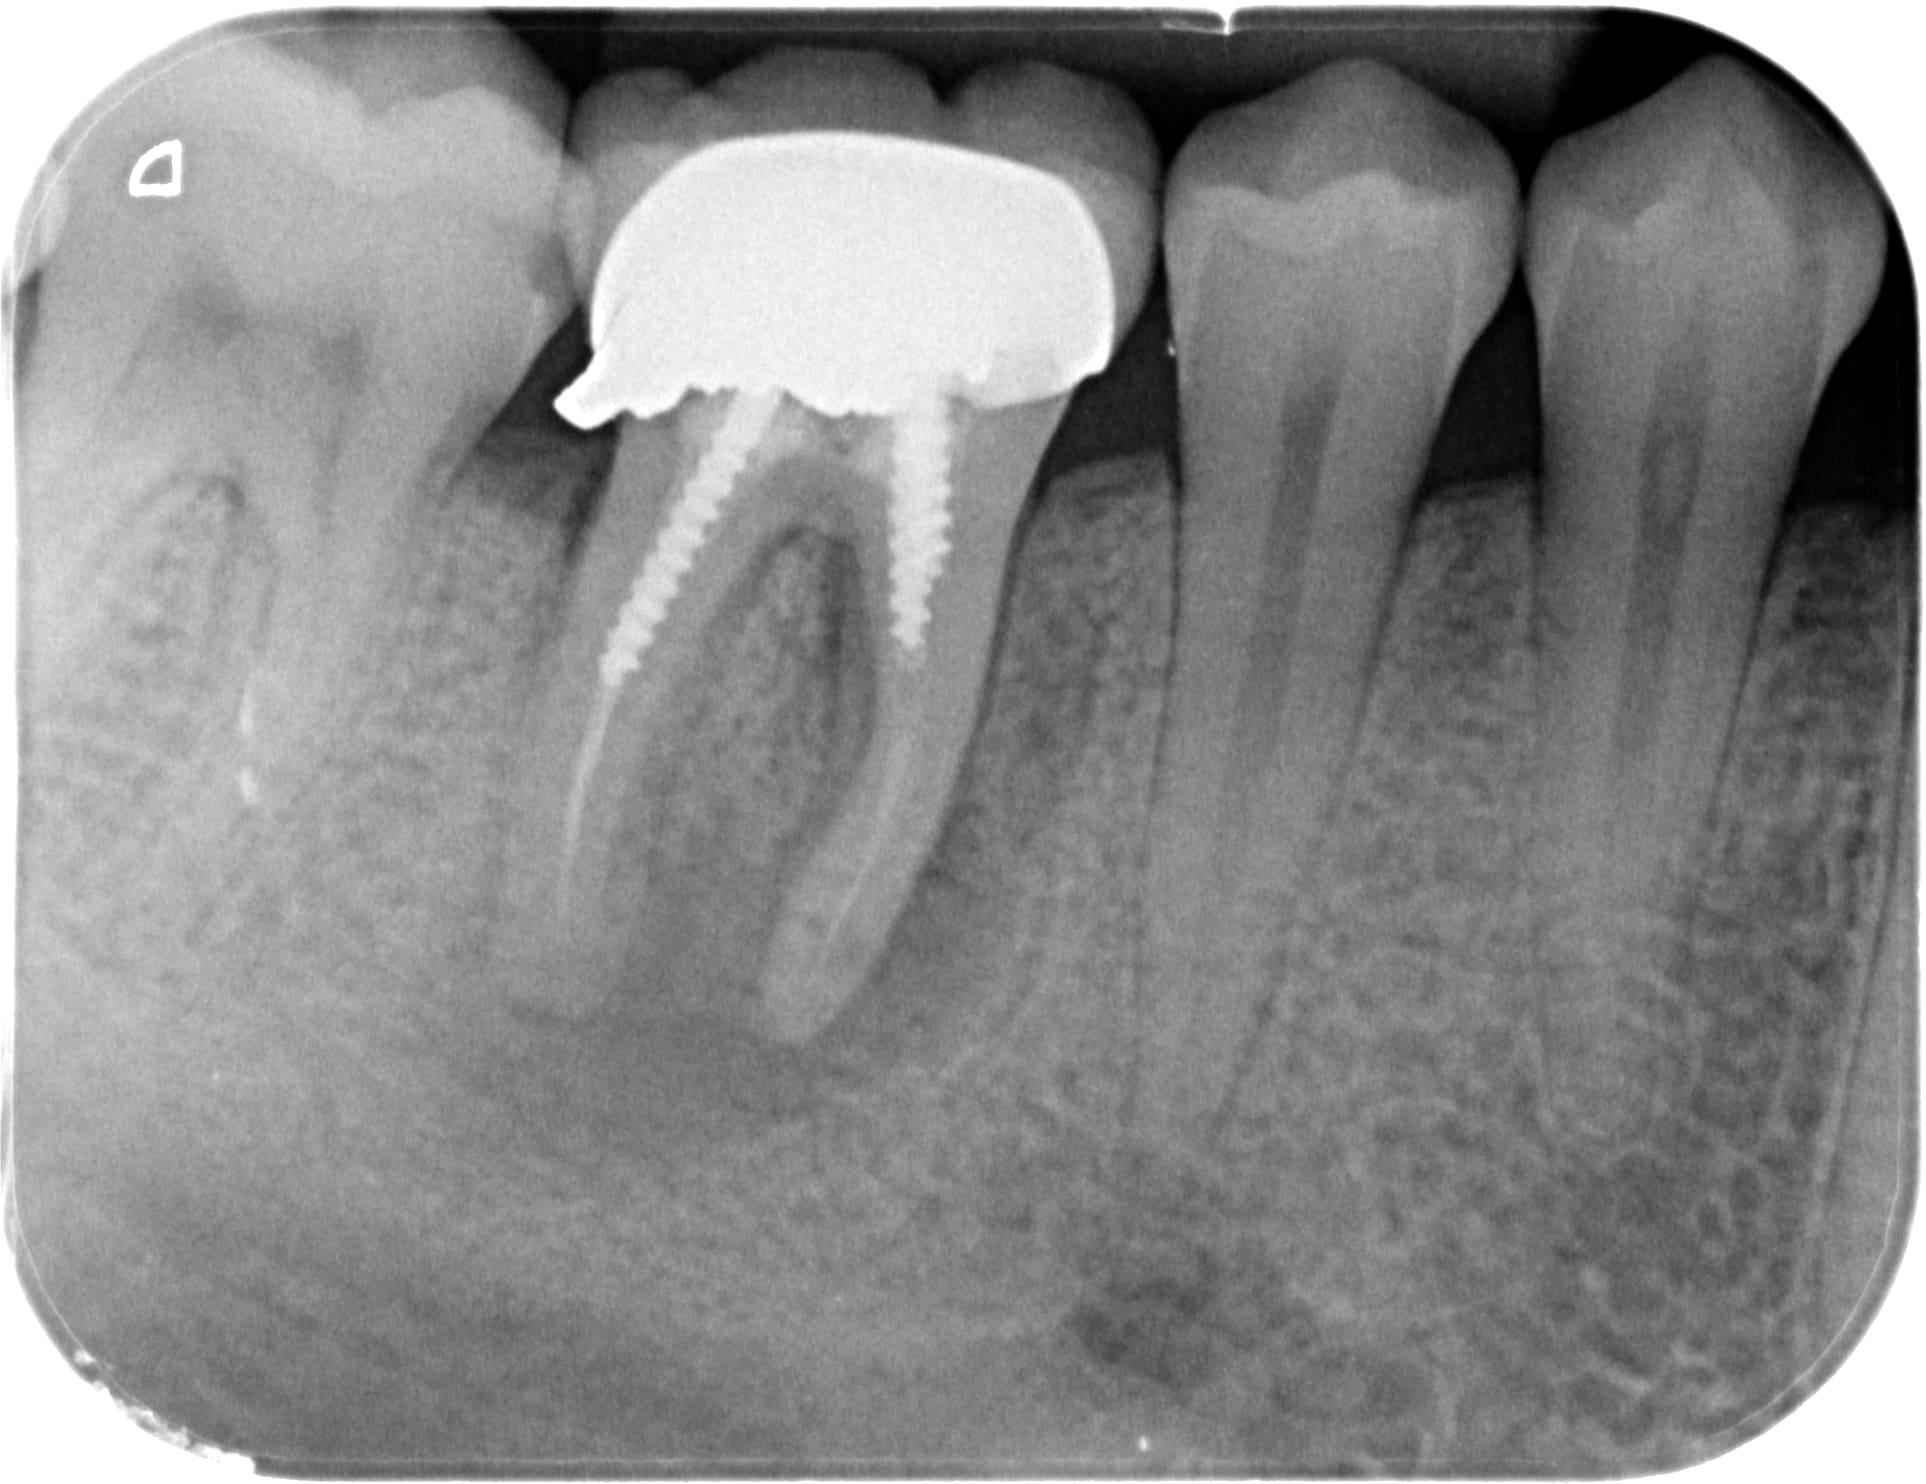

Ils vont te répondre que le tarif n'est pas un gage de qualité. Endo faite par un dentiste A = endo faite par un dentiste B, quelque soit le tarif. C'est ça le drame de notre profession : aucune évaluation qualité. Que des conneries de DPC de merde qui ne sert à rien et des déclarations d'intentions qui enfoncent des portes ouvertes.